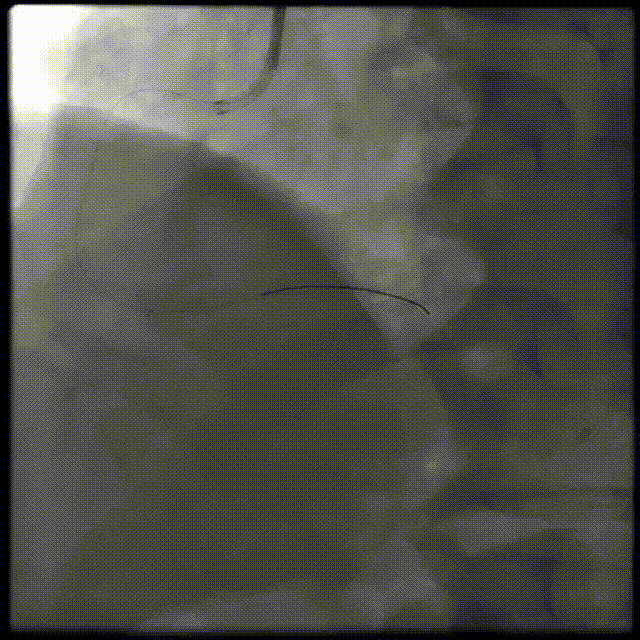

介入经过-第一次PCI旋支血运重建成功

介入经过-第二次PCI

RCA : 7F JL4 GC LCA : 6F JL4

FINECROSS MC + Pilot 50

介入经过-第二PCI

Sprinter1.25*6mm&2.5*15mm,2.5*35mm&2.5*15mm Stent

介入经过-最终造影